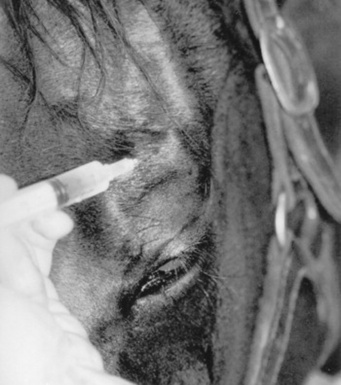

TRAUMA TO THE RETINA

Retinal tears, hemorrhage, edema, and detachment may be caused by trauma.48,49 In cases of opaque ocular media, retinal separation may be diagnosed by ocular ultrasonography (Fig. 39-9). Retinal degeneration may follow ocular trauma. Retinal hemorrhage and edema should be treated with systemic corticosteroids. With current technology, surgical repair of retinal tears, lacerations, or detachments in food animals and horses may be feasible in selected cases.

image

Fig 39-9 Ocular ultrasound of a horse eye after blunt trauma to the globe. Note the characteristic V-shaped retinal detachment.